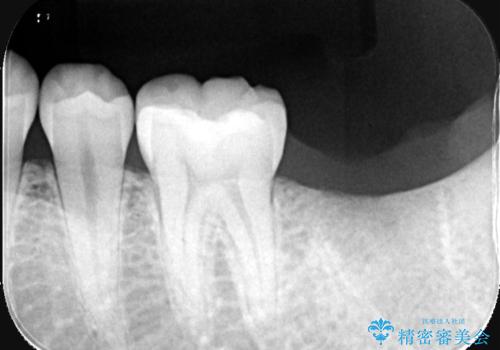

- 「歯茎の腫れ」を主訴に来院された患者様です。検査の結果、エンドペリオ病変と診断いたしました。

治療方針としては、保存的治療と抜歯後のインプラント治療の2つの選択肢をご提案させていただきました。

患者様ご自身が抜歯後のインプラント治療をご希望されたため、インプラントによる治療を行いました。